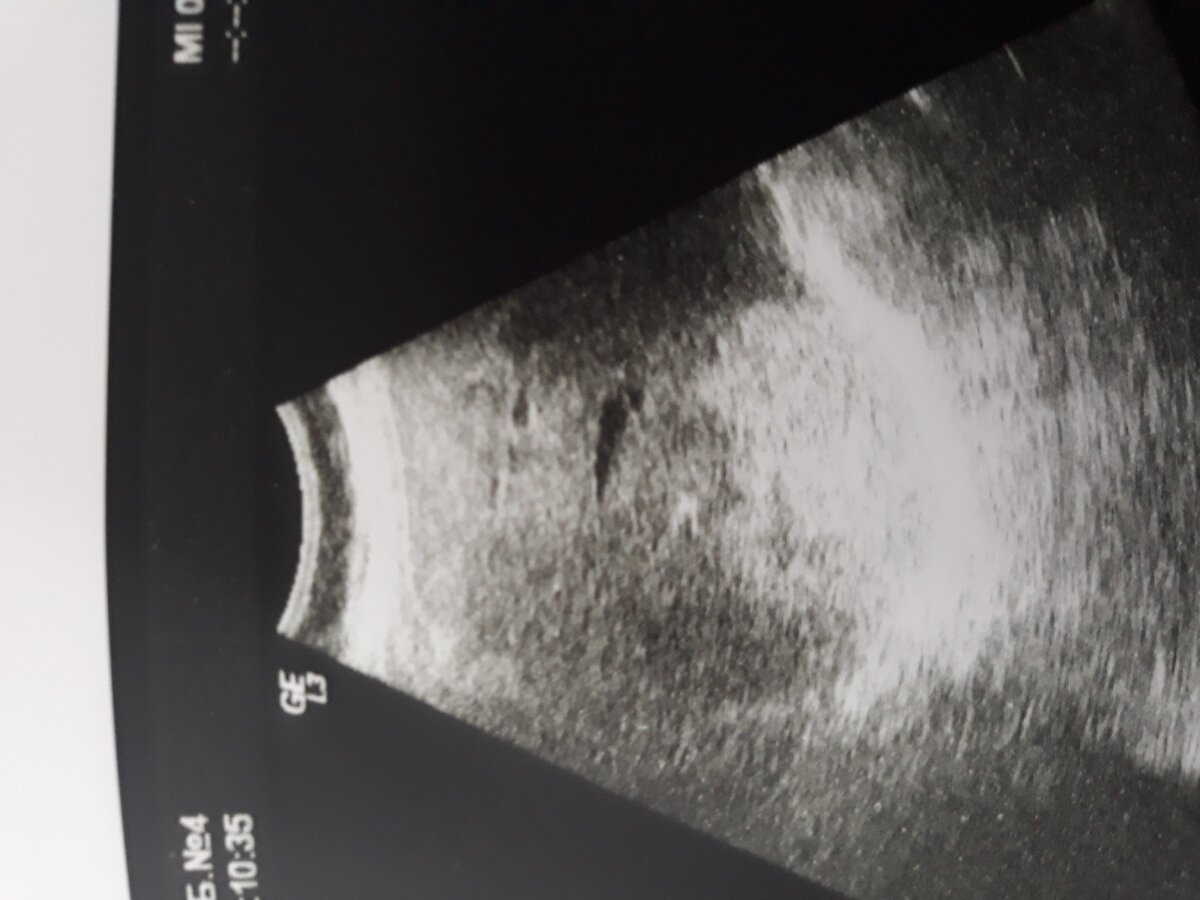

УЗ- диагноз Гемангиома печени

Выглядит довольно устрашающе.

Опытный врач УЗИ проверит ряд признаков, уверенно вынесет заключение: гемангиома печени( доброкачественное сосудистое образование). И если оно единичное, небольших размеров- действительно повода для беспокойства нет. Но, если таких образований несколько, они довольно крупные, то, хотя бы однократно, желательно пройти МРТ или КТ с контрастированием и далее ежегодно УЗ- контролировать отсутствие динамики этого образования. При чём желательно это делать у одного доктора на том же самом аппарате.